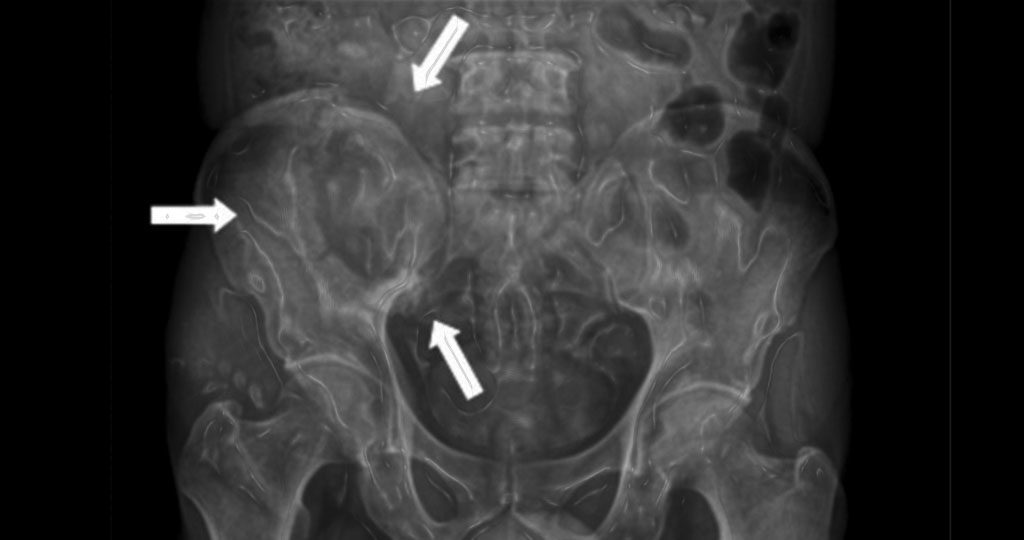

55 Multiple Osteolysen Unklarer Genese Arztekammer Nordrhein

Zufallsbefunde In Der Muskuloskeletalen Radiologie Springerlink